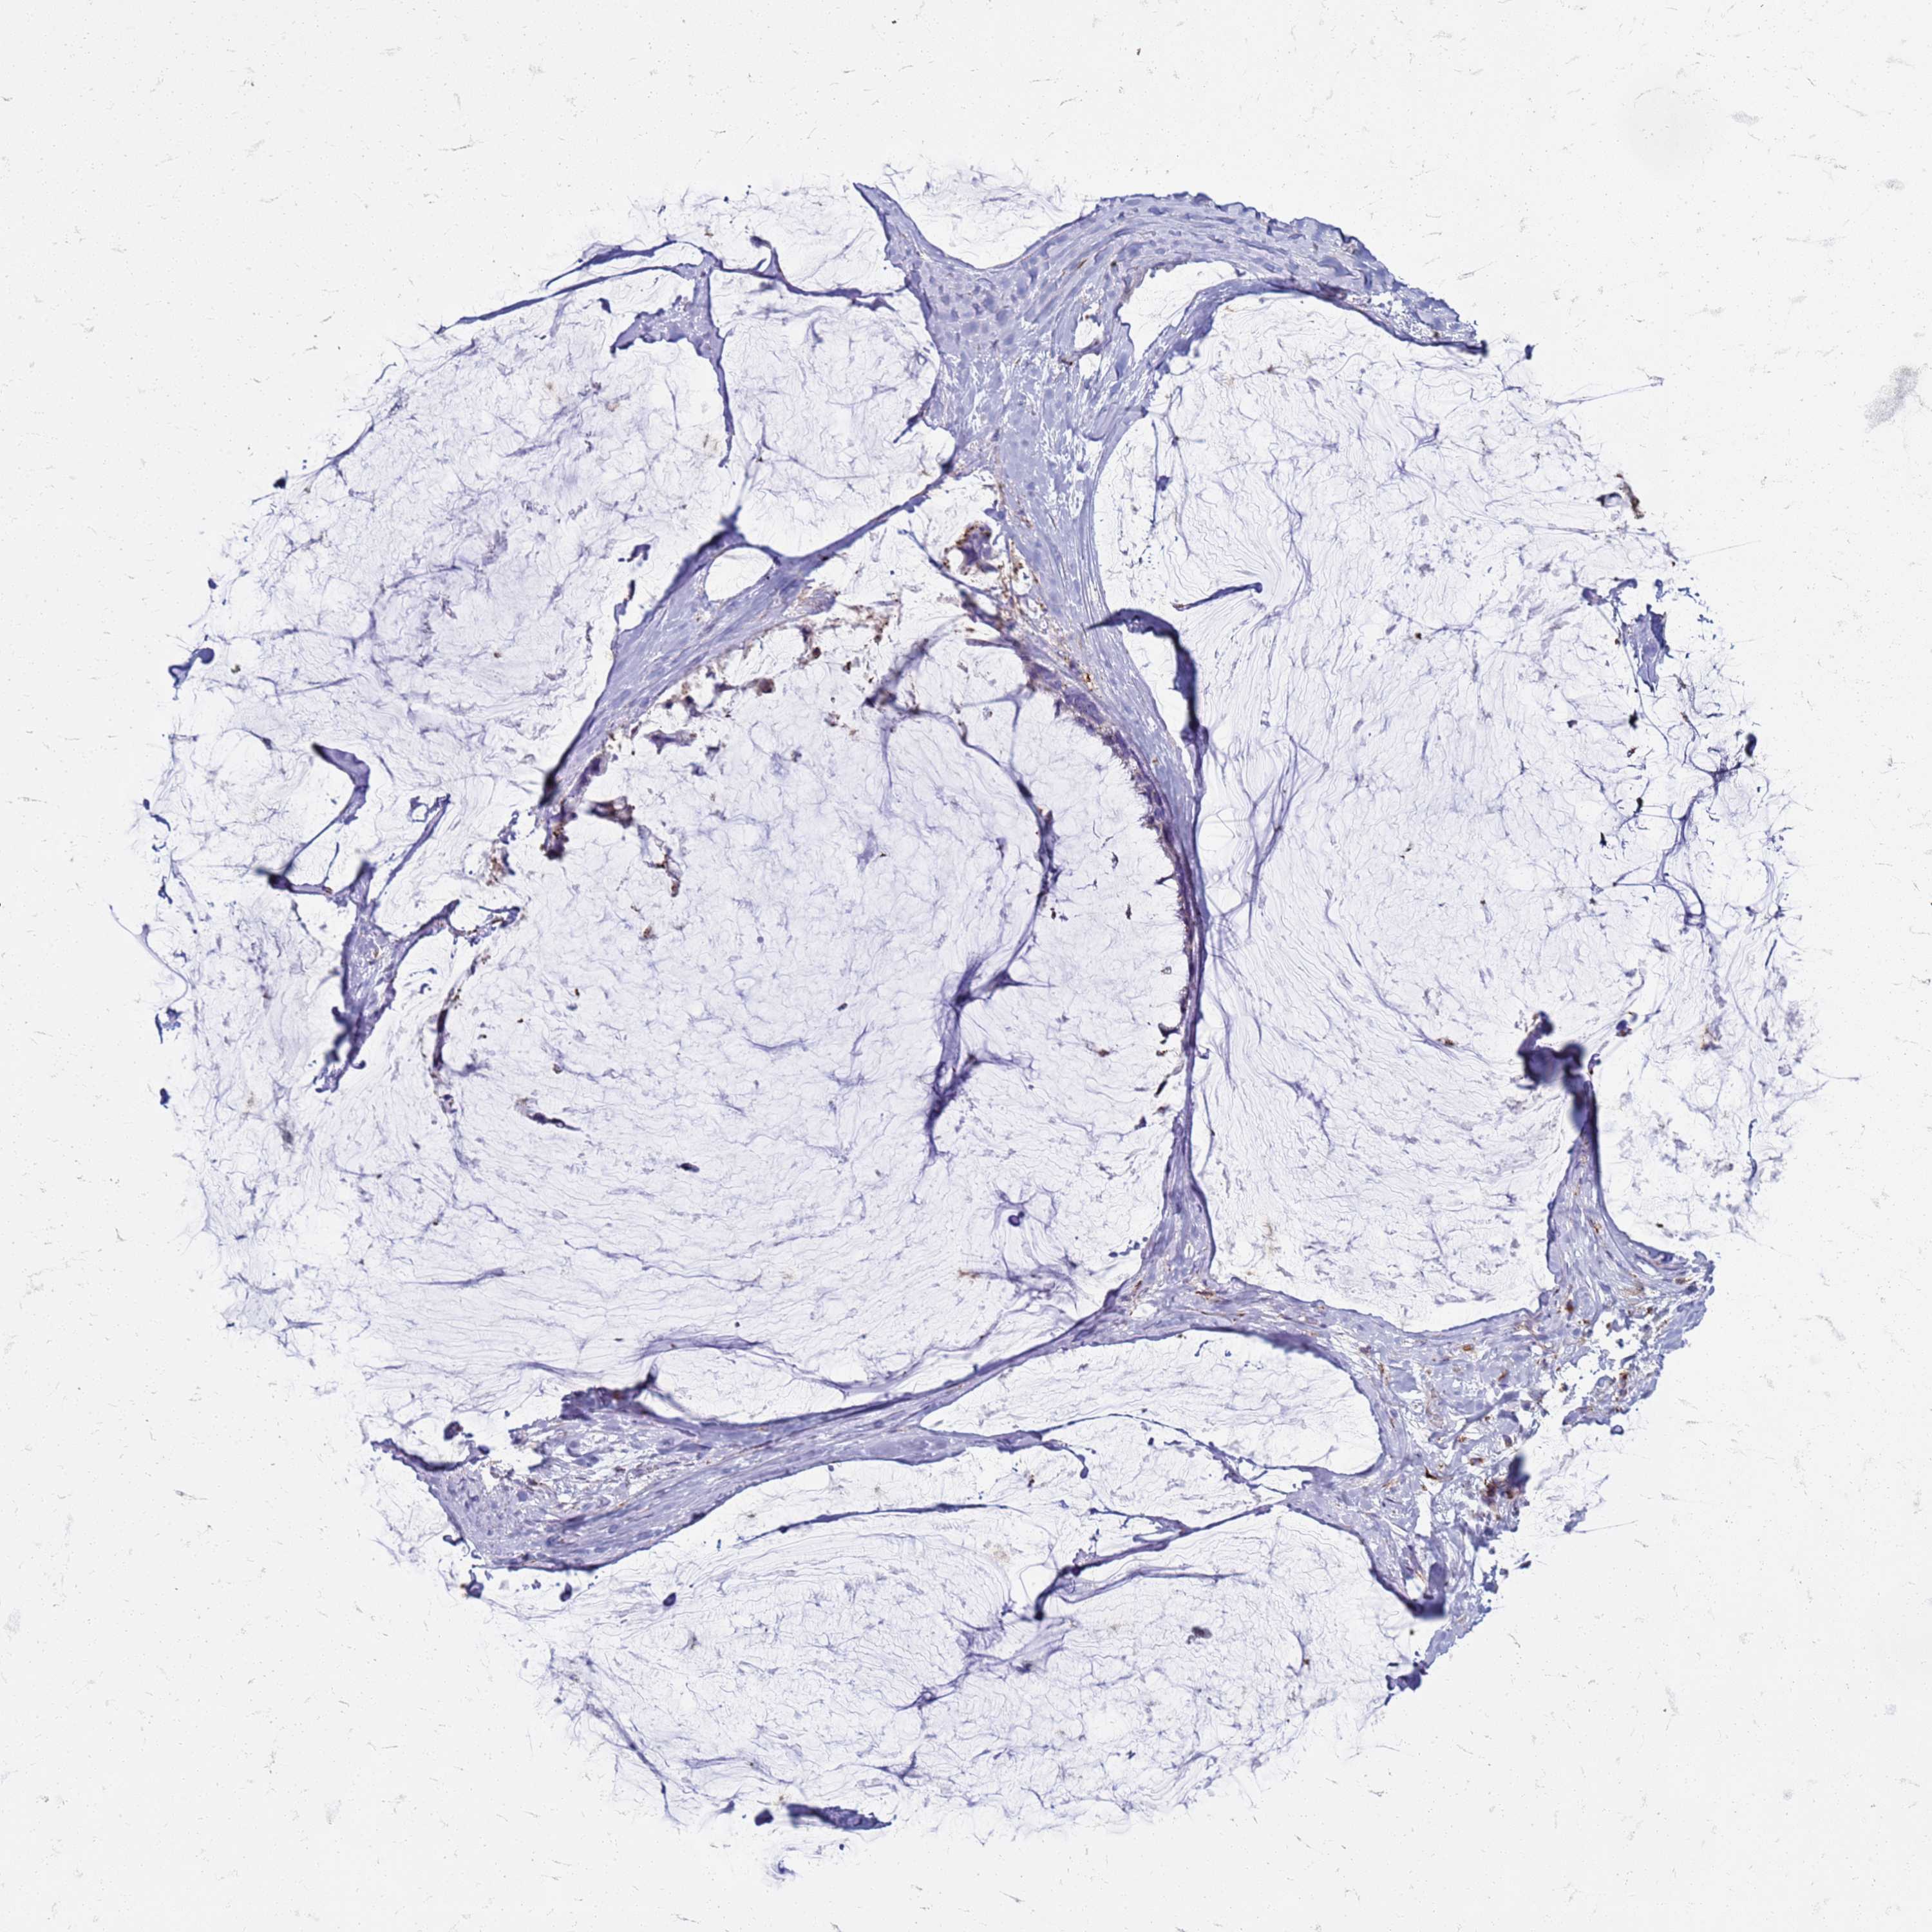

OVARIAN CANCER - Protein expressioni

A mouse-over function shows sample information and annotation data. Click on an image to view it in a full screen mode. Samples can be filtered based on level of antibody staining by selecting one or several of the following categories: high, medium, low and not detected. The assay and annotation is described here.

Note that samples used for immunohistochemistry by the Human Protein Atlas do not correspond to samples in the TCGA dataset.

Antibody stainingi

Antibody staining in the annotated cell types in the current human tissue is reported as not detected, low, medium, or high, based on conventional immunohistochemistry profiling in selected tissues. This score is based on the combination of the staining intensity and fraction of stained cells.

Each image is clickable and will lead to virtual microscopy that enables deeper exploration of all samples and also displays staining intensity scores, fraction scores and subcellular localization as well as patient and tissue information for each sample.

Antibody HPA046583

Cystadenocarcinoma, serous, NOS

Carcinoma, endometroid

Cystadenocarcinoma, mucinous, NOS

Carcinoma, NOS